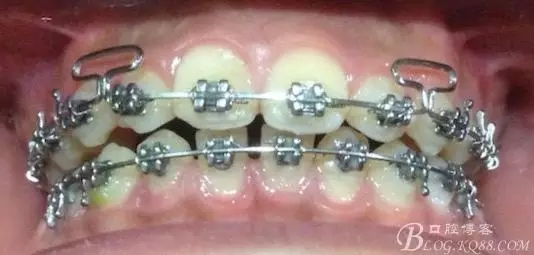

佩戴三個月的FR2, 效果奇佳!前牙基本達到淺覆蓋,淺覆合!接下來進入二期直絲弓固定正畸,排齊階段!

接下來盡管配合些雙側(cè)后牙對角牽引,咬合關(guān)系依,不盡人意。